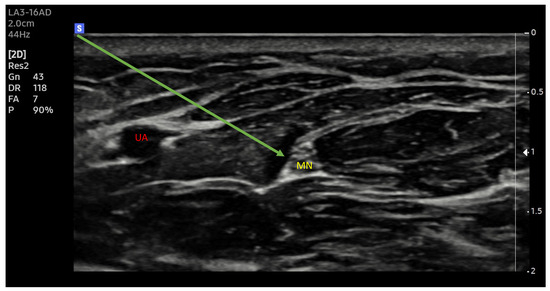

New ultrasound machines with digital image processing and customized image parameter settings make it easier to identify the selected structures (Figure 1 and Figure 2). Increasing the precision of delivery into the immediate vicinity of nerves increases the effectiveness of anaesthesia and makes it possible to reduce the dose of local anaesthetic drugs [33].

Figure 1.

Median nerve. Ultrasound transverse view. MN—median nerve, UA—ulnar artery; Arrow —needle trajectory; Arrowhead—extraneuronal needle placement.